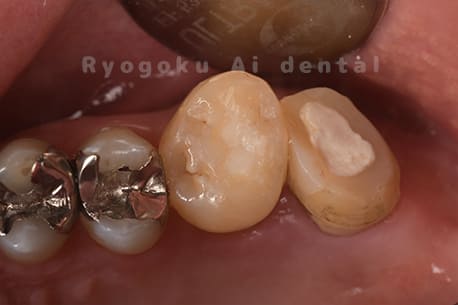

他院で右下の根の治療を行い、セラミックを被せる説明をされていたが、根の治療が終わらないため転院された患者さんです。隣の親知らずの抜歯の必要性と、根の治療を行なっている歯牙の予後が悪いため、移植治療を提案し、右下の親知らずの抜歯と同時に、右下の奥歯(7番)への移植治療を行いました。被せ物を行う必要もなく、順調に経過してます。